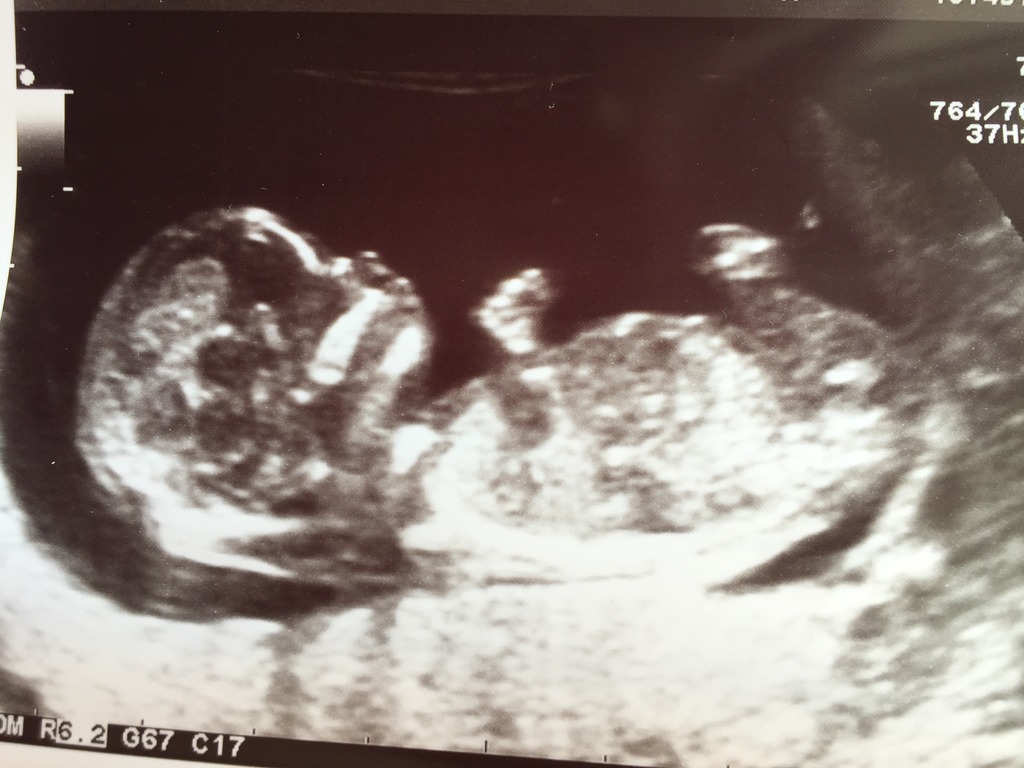

Any insights into gender gladly received. Thank you.

Sorry, no gender clues are visible. Cute baby though :happy:

What a cutie pie! Can't tell gender from this pic, sorry.